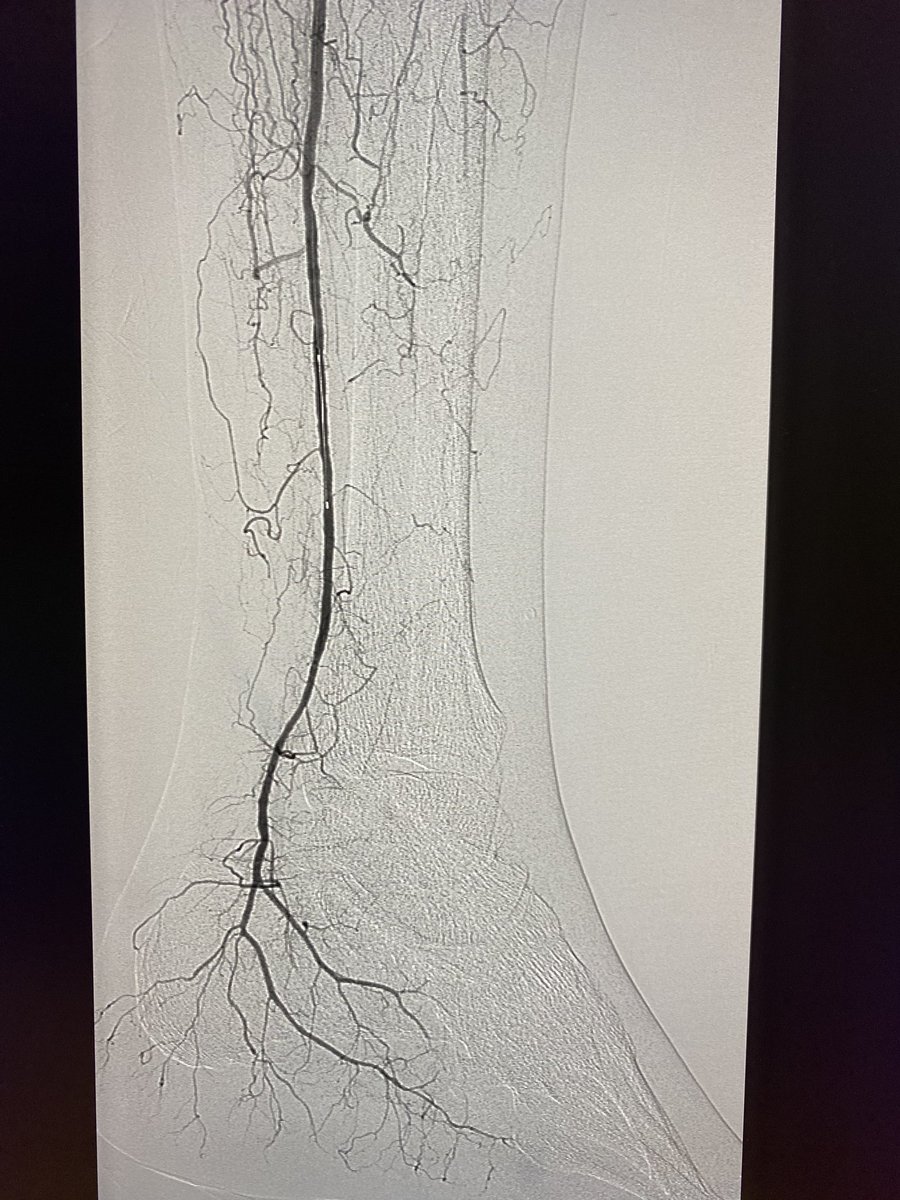

Transradial Infrapopliteal Atherectomy, Angioplasty and Stenting for Cri... youtu.be/Gf8tdMXcBls via @YouTube